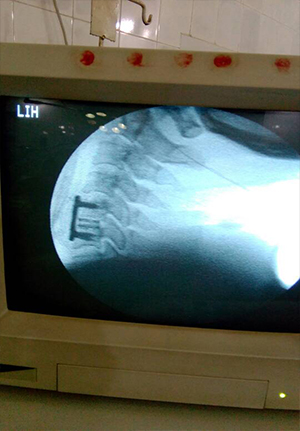

Post op picture of cervical spine fusion with cage and plate